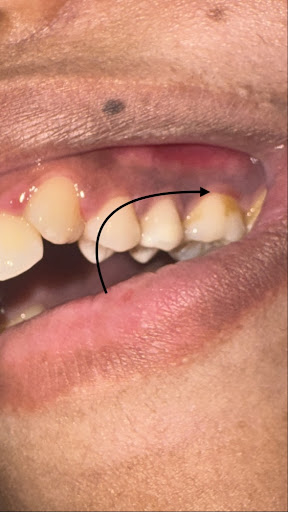

I have a constant itchy and inflamed sensation right here (MARKED BY THE ARROW). It’s very sensitive to cold and pressure, and I feel a throbbing pain here.

I’ve been chewing heavy mastic gum 3 times a day for 10 days to treat H. pylori. I think the heavy pressure may have impacted tartar or debris deep into my gum pockets.

I’ve had a tooth pulled before, and I’m very anxious about losing another one. Should I get the pocket depths checked and see if a deep cleaning (scaling) will resolve the inflammation?

looks lot of deposits,

calculus and might have cavity at the back side please contact or WhatsApp

Simple scaling n polishing will clean this along with all over